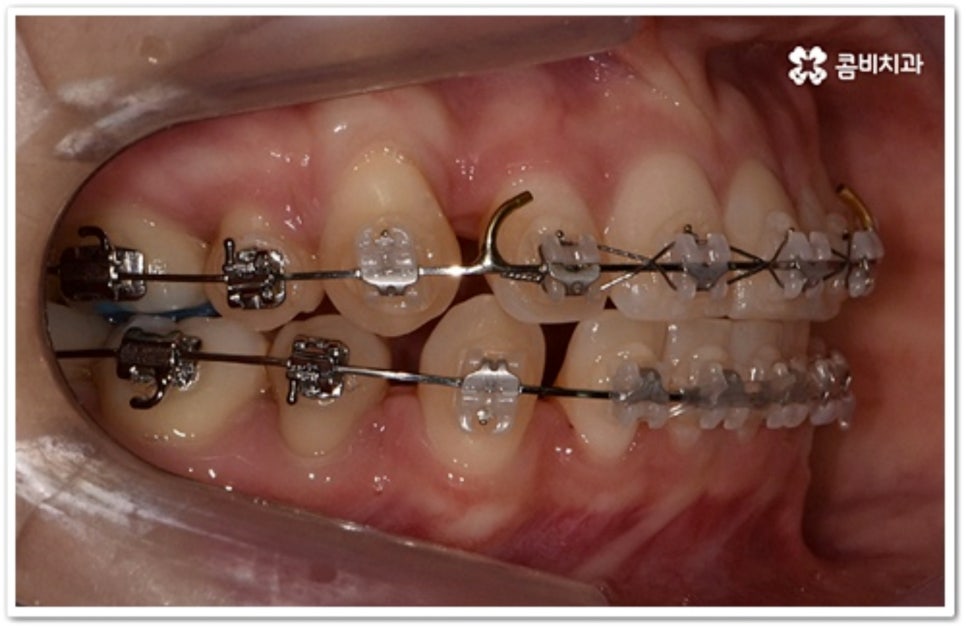

그러나 만약 덧니가 많고 부정 교합 정도가 심하거나 치아가 고르게 배열될 공간이 크게 부족하다면 덧니 발치 교정 치료를 진행하게 되는데, 이때 보통 치아 중에 기능이 가장 적은 소구치를 우선적으로 발치하게 되지만 (사진에서 확인할 수 있는 케이스) 환자분들의 상황에 따라 필요 없는 사랑니를 발치하고 어금니부터 뒤로 밀어 자리를 잡아주거나 충치 또는 짧아진 치근 등으로 심하게 손상된 치아가 있는 소구치를 우선적으로 발치하여 교정 치료를 진행하기도 하고, 필요시 임플란트와 병행하여 치료를 진행하는 경우도 있습니다. 따라서 먼저 자신의 상황에 대해서 면밀하게 검진을 받아보고 자세한 치료 계획에 대해서 의료진과 충분하게 상담해 보시는 게 좋을 거예요.

본 포스팅의 치료 케이스는 약 22개월의 치료 기간이 소요되었으며,

개인에 따라 출혈 및 부작용이 발생할 수 있고,

환자마다 치료 결과 및 기간이 상이할 수 있으므로,

정확한 치료 기간 및 치료 계획은

가까운 치과에서 상담을 받아보시길 권장 드립니다.